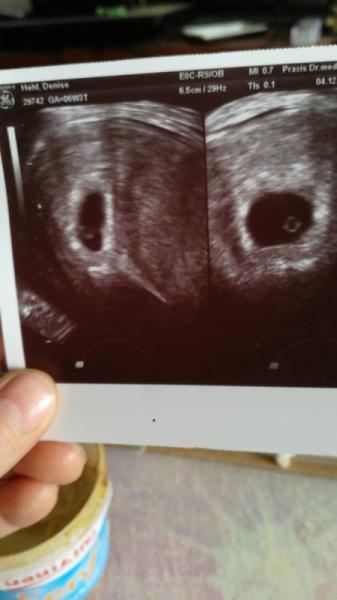

Hallo ihr da draussen heute waren wir das erstemal beim FA gestern war der test positiv der doc meinte ich sei 6+3ssw kennt jemand das es aussieht wie ne erbse oder runde kugel auf dem bild siehe Anhang???wir freuen uns richtig auch wenn es nach ner Untersuchung von um 10 bis ca 17uhr blutung gab nicht stark nur sehr leicht und es war dann vorbei. In zwei Wochen sollen wir nochmal einen Ultraschall machen pass und blutabnahme gab es heute nicht. Schönen abend ihr lieben alle werdende mamas schöne zeit mit den kleinen alle schwangeren geniesst eure zeit eurer ss

Jep, sieht bei mir so ähnlich aus war heute auch beim FA bei 6+1 oder 6+2..War auch der Dottersack mit 3 mm Embryo und ganz zaghafter Herzschlag..Also wird alles ok sein bei Dir..hänge mal mein Bild von heute mit dran..lg

Bei dir sieht man es richtig bei mir wie ne kugel richtig rund das ist irgendwie komisch aber positiv schauen

Ja, mein Bild ist ran gezoomt deshalb sieht das so aus..live sah es aus wie bei dir..Ist total normal ist der Dottersack der soll so aussehen